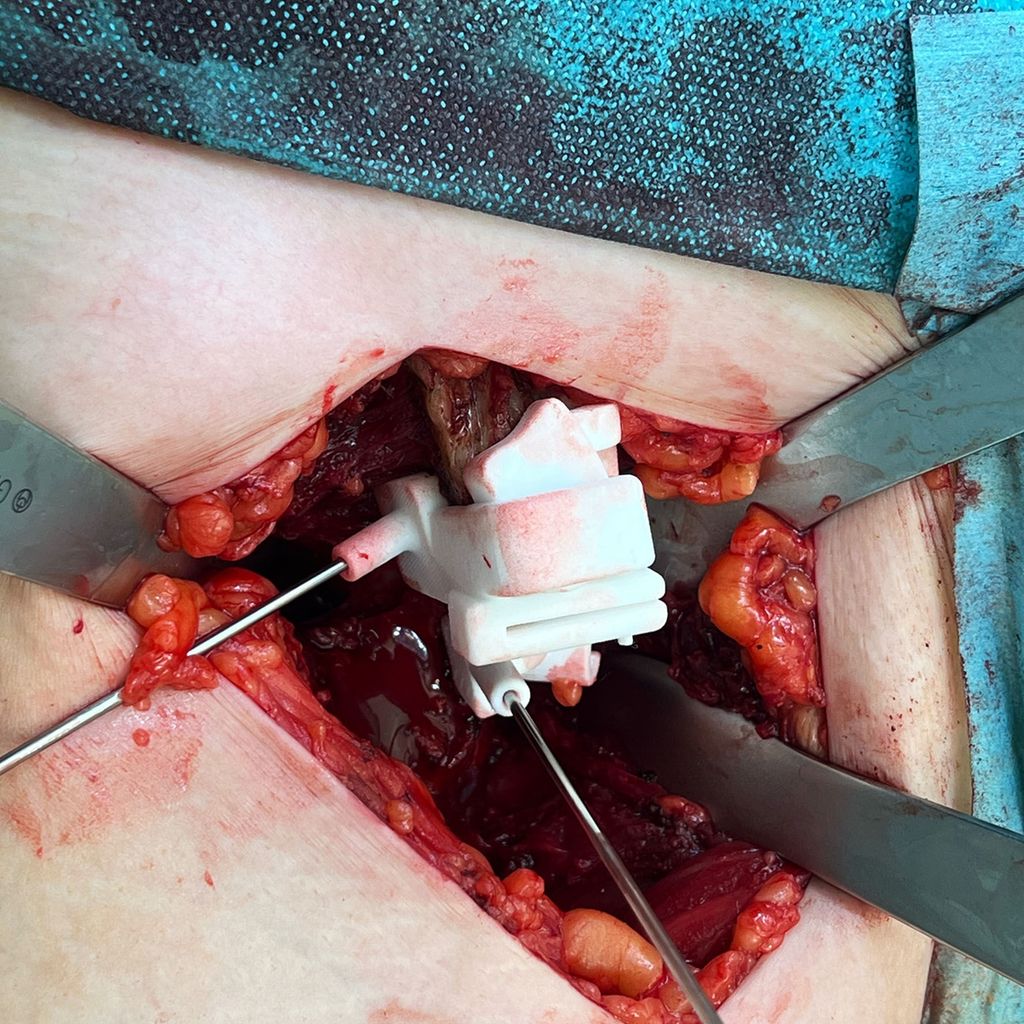

Bis jetzt gibt es zu dieser Thematik nur allgemeine anekdotische Berichte in der Literatur.6 Erste intraoperative Anwendungen von PSI-Schnittblöcken für die PAO an unserer Abteilung waren aber vielversprechend. Natürlich verlangt das Anlegen von Schnittblöcken und Korrekturblöcken mehr Weichteilrelease von den knöchernen Strukturen und unter Umständen auch einen längeren Hautschnitt mit größeren Expositionsflächen am Becken. Zudem haben wir bisher aufgrund unseres alleinigen OP-Zugangs von ventral nur Schnittblöcke für die Ilium-Osteotomie und den proximalen Anteil des Verbindungsschnittes verwendet. Eine exakte Schnittplanung in dieser Region ist aber wichtig, um hier nach vollständiger Mobilisierung des Pfannenfragments den Korrekturblock exakt so zu positionieren, dass sich das Pfannenfragment in der gewünschten Abduktions-, Flexions- und Rotationsstellung einstellen lässt. In dieser Position können über die vorgefertigten Bohrhülsen im Korrekturblock gleich die Schraubenkanäle vorgebohrt werden. Eine zeitliche Verzögerung durch die Verwendung der Schnittblöcke konnten wir insgesamt nicht beobachten.